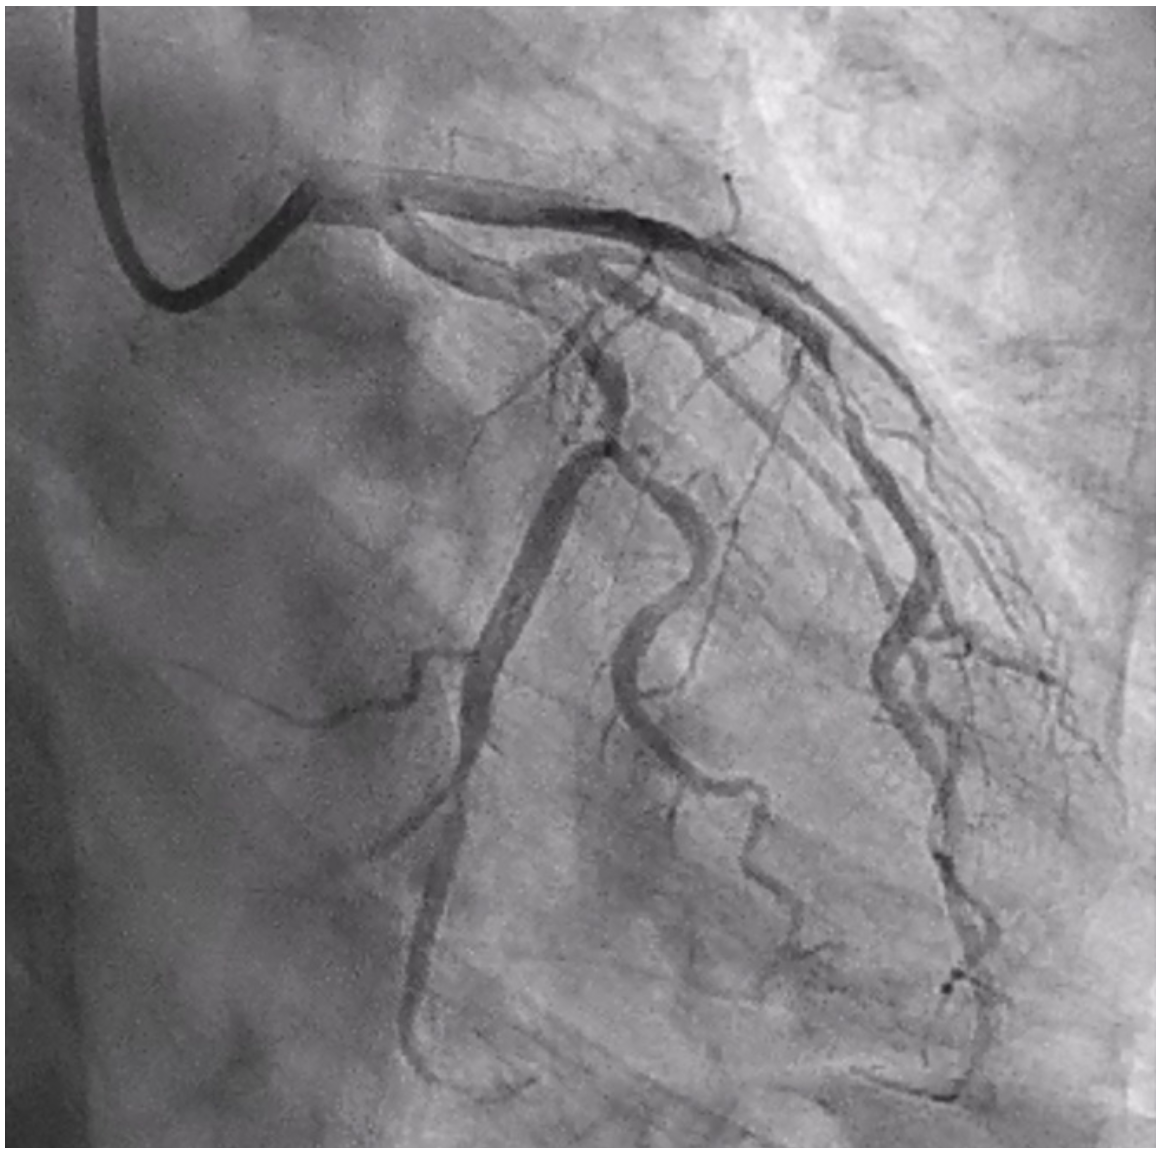

A 63-year-old male with a history significant for 50 pack years of tobacco use and a cerebrovascular accident presented with unstable angina. His electrocardiogram (ECG) showed sinus bradycardia with nonspecific ST/T wave changes (Figure 1A). Coronary angiography demonstrated significant myocardial bridging of the mid left anterior descending artery (LAD) (Video 1 and Figure 2) and nonobstructive coronary artery disease (CAD) otherwise. His left circumflex (LCX) CAD was physiologically insignificant on assessment with instantaneous wave-free ratio (Figure 3). The following day, the patient developed transient anterior ST-segment elevation myocardial infarction with a troponin of 0.5 ng/mL (Figure 1B). He was brought back for coronary angiography with intracoronary imaging. His baseline angiogram was unchanged and optical coherence tomography (OCT) was performed in the LAD, which showed evidence of acute plaque rupture within the myocardial bridging segment (Video 2 and Figure 4). There was a concern for stenting the bridging segment due to reported higher rates of target-lesion revascularization and concerns of stent thrombosis, stent fracture, and coronary perforation. Therefore, cardiothoracic surgery was consulted for unroofing of the mid LAD or surgical bypass, which are generally considered safe and effective.1,2 The left internal mammary artery was found to be a poor conduit in the operating room due to size and flow limitation. Given that the patient already had a median sternotomy, surgical revascularization with saphenous vein grafting and surgical myotomy to relieve the systolic compression were performed. The latter would facilitate durable percutaneous revascularization options in the future.